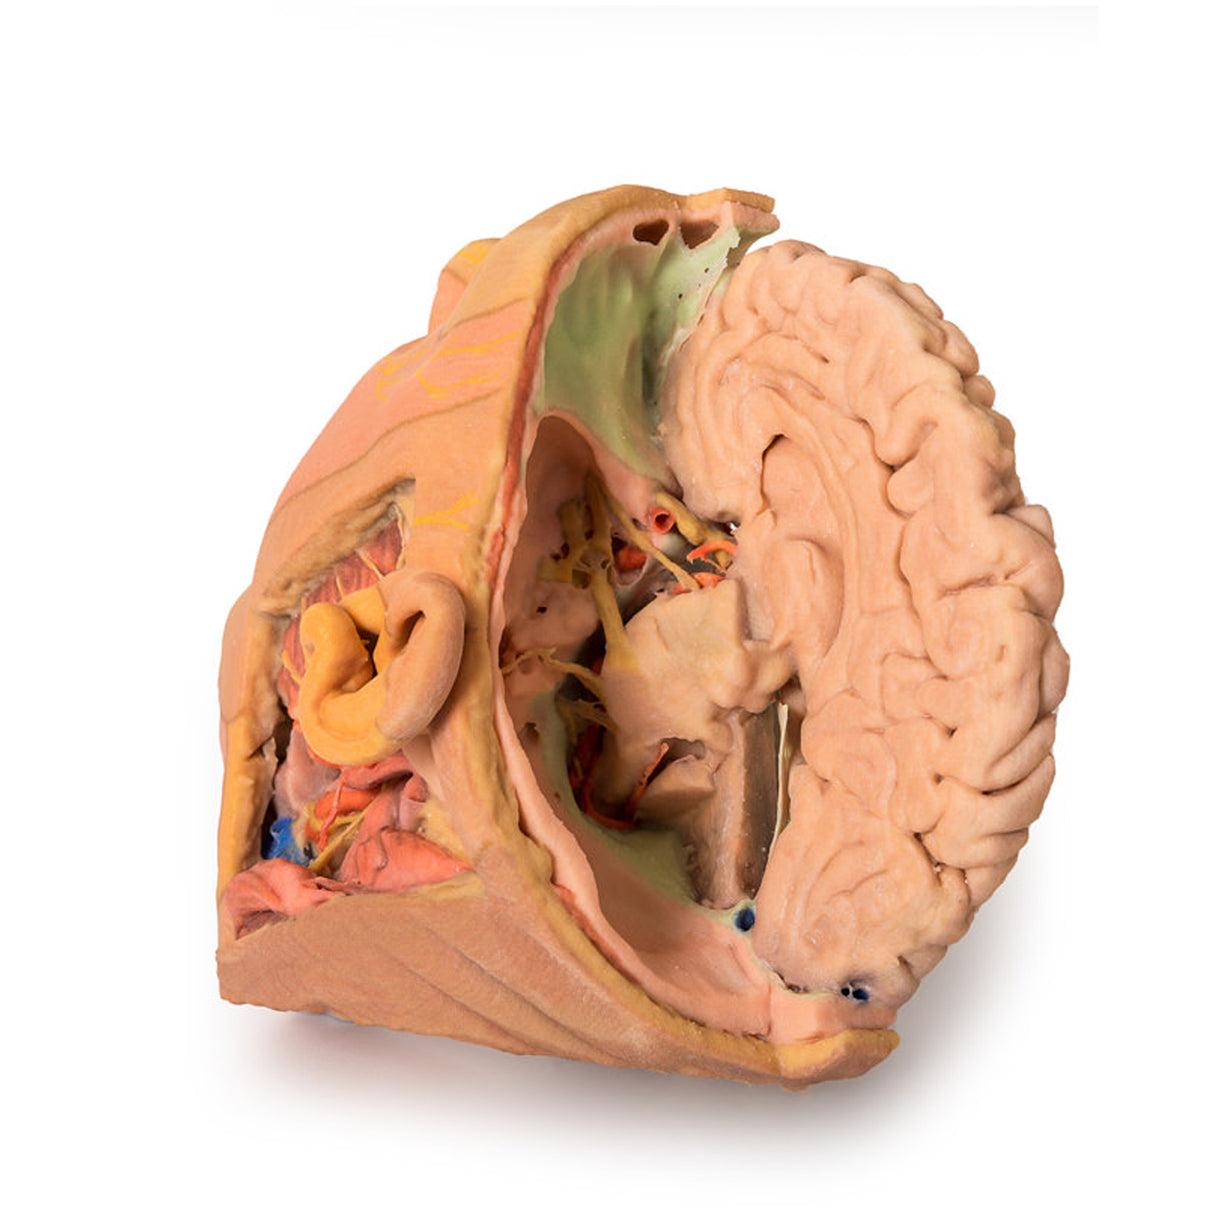

This 3D print provides a detailed view of head and neck anatomy, showing different structures depending on the perspective.

Lateral Face and Parotid Region

A window exposes the parotid region, with the pinna intact and the mastoid process revealed by reflecting the sternocleidomastoid (SCM). The parotid gland is removed to display hidden structures, including the posterior digastric, masseter muscle, and mandibular condyle in the TMJ. The external carotid artery (ECA) and its branches, internal jugular vein (IJV), hypoglossal, vagus, spinal accessory, and facial nerves are clearly visible. Facial dermatomes are illustrated via the trigeminal nerve branches.

Brain and Cranial Cavity

The medial cerebrum shows the corpus callosum, thalamus, sulci, and gyri, while parts of the cerebellum are removed to expose the cranial fossae floor and fourth ventricle. The cavernous sinus, sella turcica, and intracranial course of cranial nerves II, III, V, VII–X, XI are displayed, including the facial canal and geniculate ganglion.